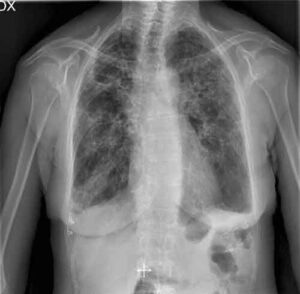

Ha un nome complicato, "Broncopenumopatia cronica ostruttiva", per questo viene spesso chiamata, più semplicemente, "Bpco". Tosse, catarro e affanno, generalmente...

Un semplice esame del sangue per predire lo sviluppo dell'enfisema, patologia mortale che causa la distruzione degli alveoli polmonari, prima...